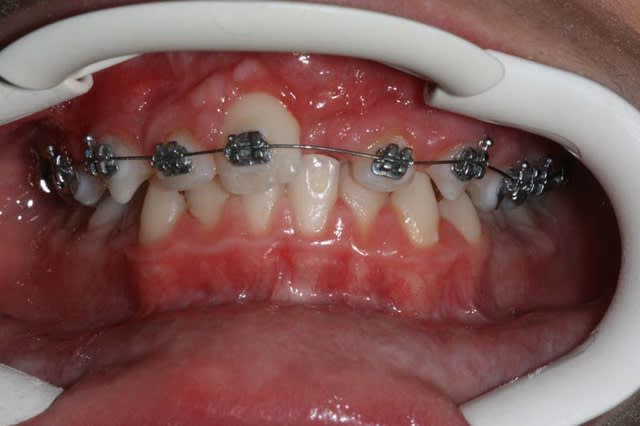

La suite n’est plus qu’une formalité avec les frictions faibles

6 s7xn9x - Eugenol